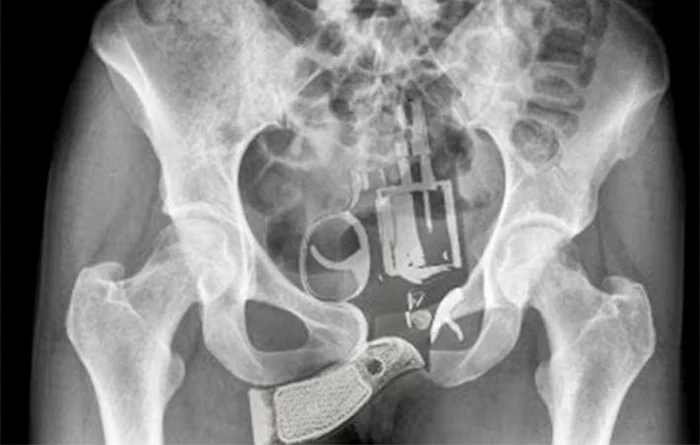

O femeie de 34 de ani, din statul american New Mexico, a reuşit să strecoare un pistol în puşcărie, ascuns în vagin.

Josephine McAllister fusese arestată în decembrie 2014 pentru posesie de carduri false. Americanca a reuşit să-i păcălească pe poliţiştii care au reţinut-o, însă angajaţii centrului de detenţie din Albuquerque au descoperit arma de foc pe care aceasta o avea ascunsă în organul ei genital.